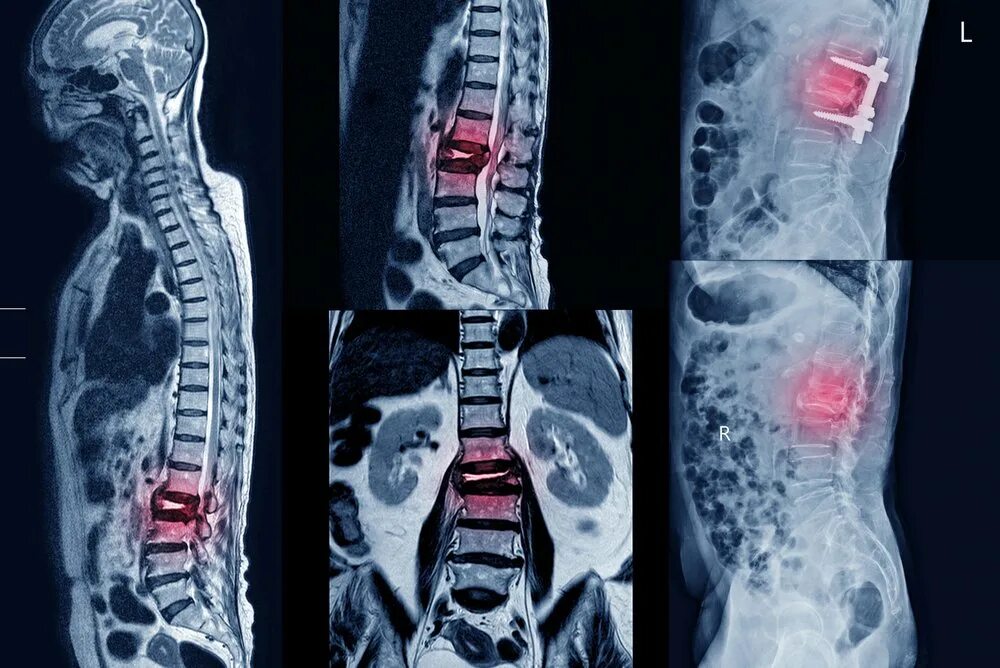

Можно ли делать мрт после операции